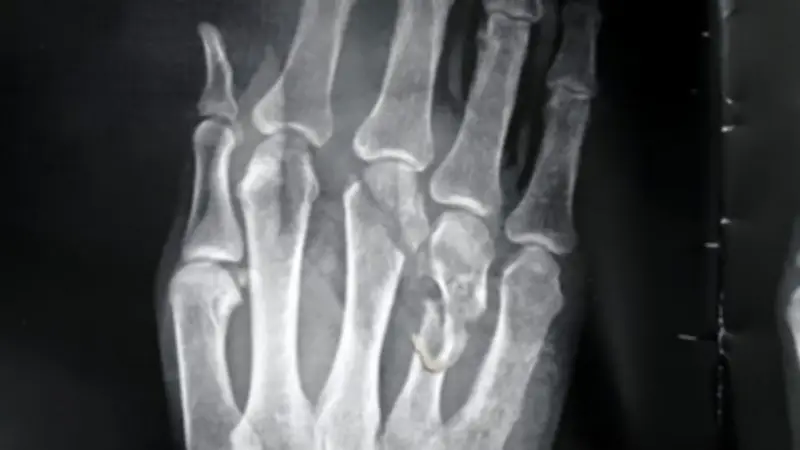

أجرى الجراحة الدكتور أحمد عبدالرزاق، استشاري جراحة العظام، والدكتور محمد رأفت، استشاري جراحة العظام أيضاً، بدعم من فريق طبي مكون من الدكتور أحمد عاشور، استشاري التخدير، والدكتور أحمد حسن، طبيب مقيم في جراحة العظام، والممرضة علا أحمد من هيئة التمريض. وأوضح الدكتور محمد الديب أن فحص الحالة كشف عن إصابات خطيرة تشمل بتر جزئي باليد اليمنى، مع قطع كامل في الأوتار الباسطة لليد والأصابع، وتهتك بالأعصاب، وفقدان جزء من الجلد، بالإضافة إلى كسور في المشطية الثانية والثالثة والرابعة باليد اليمنى.

على الفور، تم حجز الحالة وإجراء الفحوصات اللازمة، بما في ذلك الأشعة، لتجهيز المريض لدخول غرفة العمليات. نفذ الفريق الطبي تدخلاً جراحياً دقيقاً شمل إصلاح الأوتار المقطوعة، وتثبيت الكسور، والتعامل مع الإصابات المصاحبة، مع توفير الدم والعلاج اللازم للمريض. وأكد الديب أن الجراحة تكللت بالنجاح، مما أدى إلى إنقاذ اليد من البتر وتحسن ملحوظ في الحالة الصحية للمريض، الذي خرج من المستشفى في حالة مستقرة.